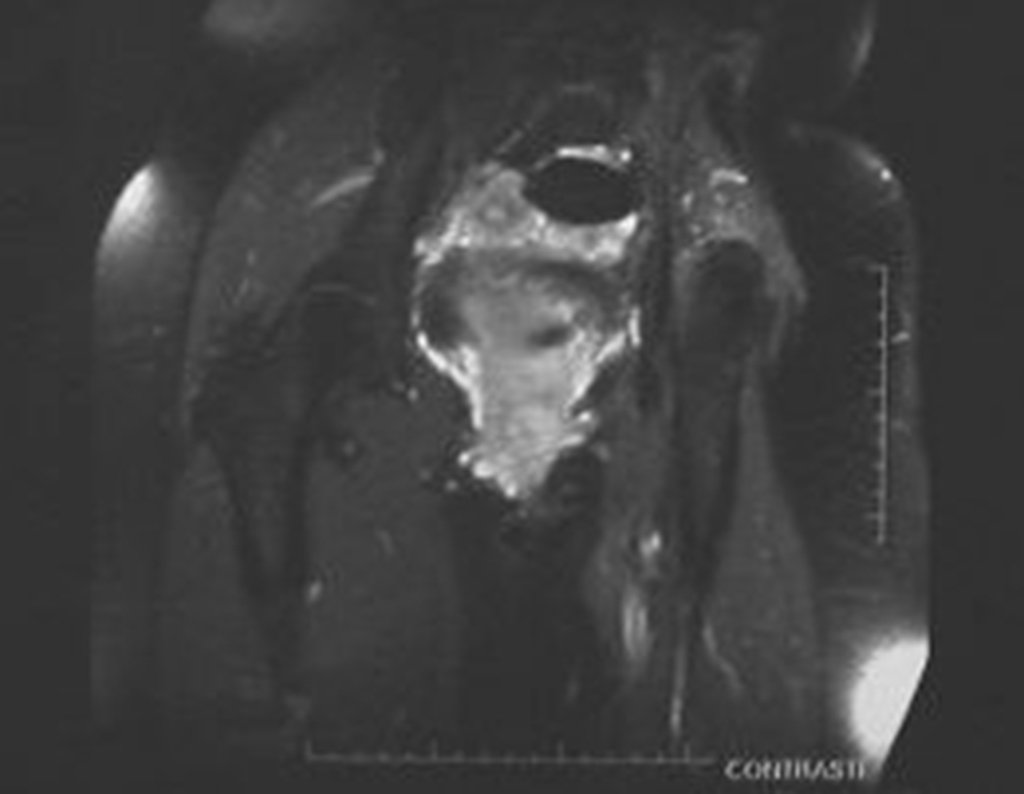

Ressonância Magnética (RM)

- RM axial e coronal em T1: Apresentou baixo sinal com grande tumor extra cortical, comprometendo a tábua interna e externa do ilíaco direito.

- RM axial e coronal em T2: Sinal alto com grande tumor extra cortical.

- RM axial T1 spir: Com supressão de gordura, evidenciou reação periosteal em espículas e focos de calcificação.

- RM axial T1 com saturação de gordura e contraste: Mostrou uma espessa área de captação devido à capa de cartilagem neoplásica maligna ao redor da lesão.